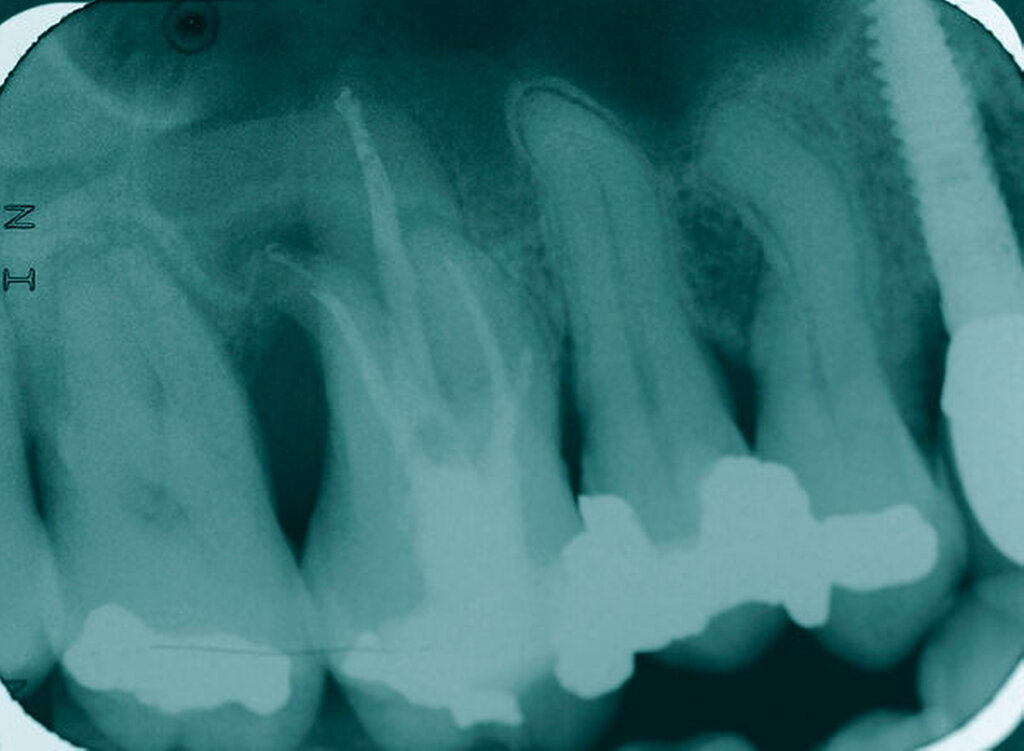

Eine 46-jährige Patientin klagte 2014 über wiederkehrende Beschwerden an Zahn 16, die sich auch nach einer endodontischen Behandlung nicht besserten. Wiederholt waren submuköse Abszesse aufgetreten. Lokalisiert war die Sondierungstiefe stark erhöht, was auf eine Längsfraktur der mesiobukkalen Wurzel hindeutete. Die Patientin wurde über die Möglichkeiten der Amputation der mesiobukkalen Wurzel sowie alternativ der Extraktion des Zahnes aufgeklärt und entschied sich für den Versuch des Zahnerhalts mittels Teilamputation der mesiobukkalen Wurzel.

Im Rahmen der Versorgung erfolgte auch ein Austausch der Extensionsbrücke 16–14 durch Einzelkronen auf 16 und 15 sowie einer Implantatversorgung mit Einzelkrone in Regio 014. Der Erhalt des Zahnes 16 ermöglichte so eine wenig invasive Versorgung des ersten Quadranten mit guter Hygienefähigkeit. Alternativ wäre bei Extraktion des Zahnes die Versorgung beispielsweise mit einer ausgedehnten Brückenkonstruktion von 13–17 oder einem weiteren Implantat in Regio 016, vermutlich mit (indirektem) Sinuslift, notwendig gewesen. So konnte der Fall minimalinvasiv zufriedenstellend gelöst werden. Die Patientin ist seit dem Eingriff beschwerdefrei und kommt gut zurecht. Die Situation ist nun seit sechs Jahren stabil.